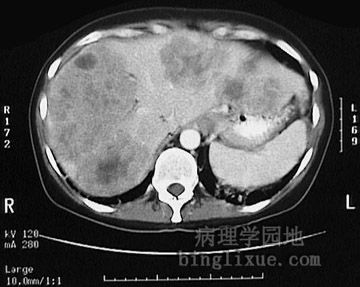

This computed tomographic (CT) scan without contrast of the abdomen in transverse view demonstrates multiple mass lesions resulting in a markedly enlarged liver extending from right to nearly the left side of the upper abdomen. These are metastases from a colonic adenocarcinoma. A normal sized spleen is seen at the lower left.

图示:结肠腺癌肝转移CT影像

腹部横断面CT扫描图像显示多个肿块,致使肝脏体积明显增大,从右侧几乎延伸至左侧边缘。左侧(图的右下角)下部可见正常大小的脾脏。